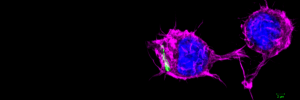

Navorsers sal byvoorbeeld gedurende hierdie projek opgelei word in die nuutste molekuêre beeldingstegnieke. Die mikroskopiese beeld hierbo toon die verskil tussen 'n makrofaag wat deur tuberkulose geïnfekteer is (links) en 'n gesonde sel (regs). Foto verskaf deur Naomi Okugbeni, Dr Ben Loos en Dr Craig Kinnear van die Universiteit Stellenbosch.